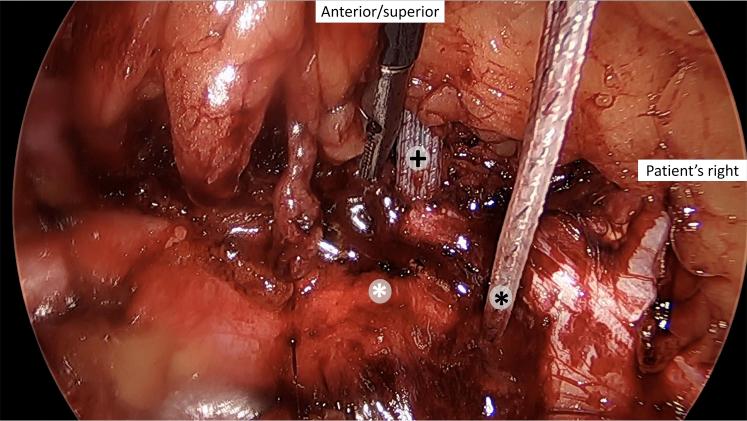

Laparoscopic Treatment of Pubic Symphysis Instability With Anchors and Tape Suture.

Patients with pubic symphysis instability who had failed nonoperative treatments may benefit from surgical repair. This disease process is rare, most commonly seen in postpartum women and athletes, and its surgical treatment is invasive and nonphysiological. Currently described surgical interventions, although limited, include plating, which provides an overly rigid construct with the risk of failure and possibly poor long-term outcomes particularly in athletes, and treatments such as curettage, more commonly used in the treatment of osteitis pubis. An emerging option is minimally invasive laparoscopic fixation using knotless anchors with a tape suture in a crisscross configuration. This possibly allows more physiological movement of the pubic symphysis in a less invasive manner. A detailed technical description and discussion of the technique are provided.

耻骨联合不稳定且非手术治疗失败的患者可能从手术修复中获益。这种疾病过程罕见,最常见于产后女性和运动员,其手术治疗具有侵入性且不符合生理状态。目前描述的手术干预措施虽然有限,但包括钢板固定,这会提供过于刚性的结构,存在失败风险,尤其在运动员中可能导致不良的长期预后,还有诸如刮除术等治疗方法,更常用于耻骨炎的治疗。一种新兴的选择是使用无结锚钉和带缝线以交叉配置进行微创腹腔镜固定。这可能以微创方式使耻骨联合实现更多的生理性活动。本文提供了该技术的详细技术描述和讨论。